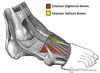

What is this muscle?

Rhomboid major